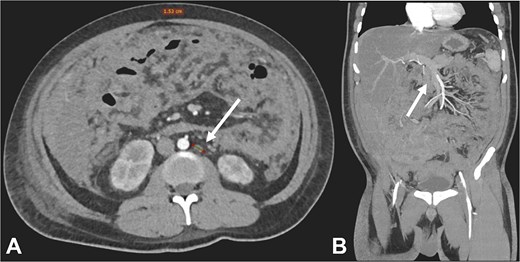

Postoperatively, suspected PTB was evaluated. Diagnostic tests, including sputum smear microscopy and GeneXpert MTB/RIF, peritoneal fluid culture and microscopy, and auramine-rhodamine stool staining, were negative. Thoracoabdominal CT (Figs 2 and 3) revealed generalized PC, plaque-like involvement at the hepatic flexure of the colon, and inflammatory lymph nodes. Histopathology provided the definitive diagnosis of NHL (Figs 4 and 5). Following an uneventful postoperative recovery, the patient was discharged after one week and referred to a tertiary care center, where chemotherapy was initiated, leading to significant improvement.

Contrast-enhanced CT in the venous phase: Axial view (A) and coronal reconstruction (B) demonstrated nodular thickening of the peritoneum with vascular enhancement, peritoneal implants measuring up to 6 mm (arrow), and plaque-like implants along the splenic margin (head arrow).